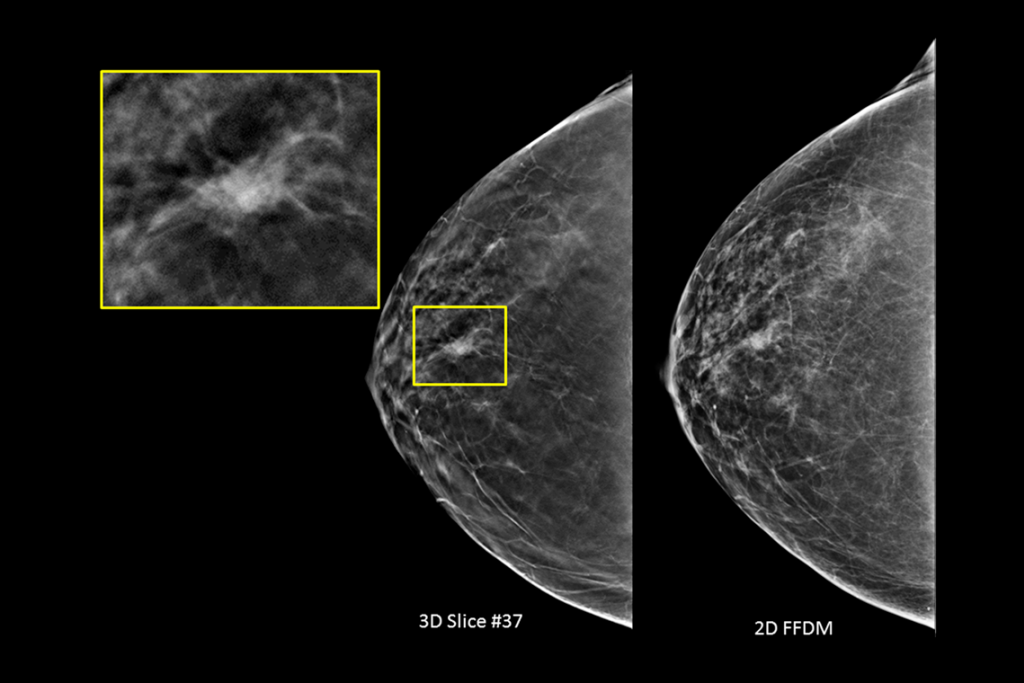

Clinical Images